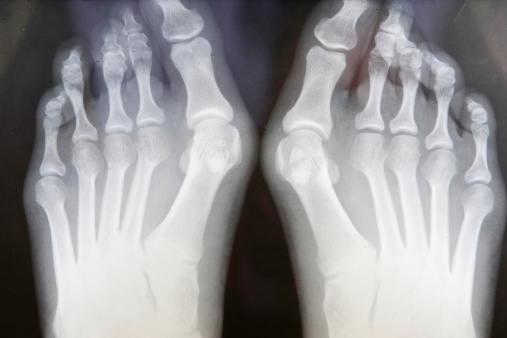

¿Qué son los juanetes y cómo se tratan? Aquí lo que debes saber ow.ly/SLDr50AIW5N